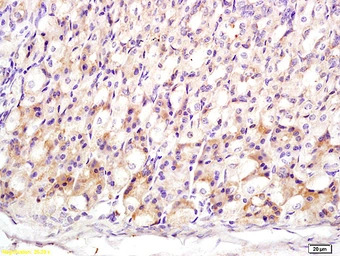

IHC-P analysis of mouse stomach tissue using GTX60188 MT3 antibody.

Dilution : 1:200